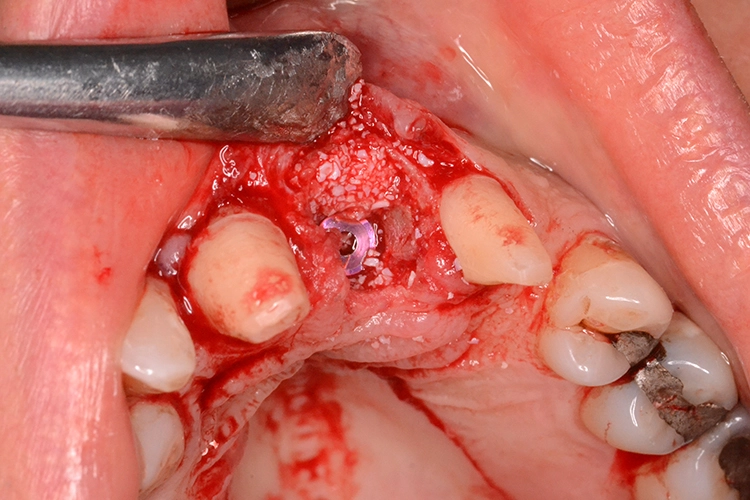

Im präoperativ angefertigten DVT (Abb. 3b und c) zeigte sich um die Wurzelspitze ein chronisches Entzündungsgeschehen, welches die vestibuläre Lamelle im apikalen Wurzelbereich des Zahnes 23 komplett aufgelöst hat. Da jedoch der Bereich direkt apikal von 23 nicht vom Geschehen betroffen war, fiel die Entscheidung zur Sofortimplantation auch, da der Patient blutverdünnende Medikamente einnehmen musste, welche durch Kombination von Extraktion und Implantation nur einmal abgesetzt werden mussten. In diesem Fall war aufgrund des Knochendefektes die Bildung eines Volllappens mit Entlastung unumgänglich.

Dr. Opitz

Anschließend wurde der Knochendefekt mit kortikospongiösem Knochengranulat aufgefüllt und mit einer langsam resorbierenden Kollagenmembran versorgt (Abb. 3e und f). Das OP-Gebiet musste im Anschluss aufgrund der Augmentation vollständig gedeckt werden (Abb. 3g).